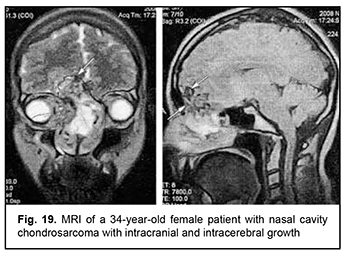

Leiomyosarcoma of the lateral scull base is a tumor with an invasive/ expansive growth pattern, intradural and intracerebral extension, and fusion with surrounding tissues (Fig. 16). Osteoblastoclastoma is a primary bone tumor that may run a benign or malignant course and is characterized by a recurrent growth pattern. Large osteoblastoclastomas frequently bleed and display significant intracranial and extradural extension (Fig. 17). Chordomas develop from remnants of the notochord and can arise at any level of the cranioaxial axis, most commonly, the sphenoidal or sacral level. They have an aggressive and invasive growth pattern with a high risk of recurrence and exhibit early epidural extension. As time goes on, a chordoma (especially, a recurrent chordoma) acquires signs of invasive growth and becomes characterized by intradural and subdural extension. Skull base chordomas are tumors extending centrally, as opposed to skull base chordosarcomas that extend in a lateral direction. Chondroma is a benign tumor that originates from the cartilaginous tissue, shows slow epidural growth and may undergo malignant transformation to chondrosarcoma. In addition, chondroma is characterized by recurrent growth pattern and, with recurrence or after undergoing transformation to chondrosarcoma, it displays invasive growth into the dura mater. The typical location of chondroma is at the craniovertebral junction (Fig. 18). Similar to chondroma, chondrosarcoma runs a course with an expansive growth pattern that is accompanied by bony destruction of the central skull base (sphenoidal sinus, sella turcica, clivus of the occipital bone, and posterior ethmoid labyrinth). However, as opposed to chondroma, chondrosarcoma grows invasively, most commonly extends into the epidural space and frequently recurs, exhibiting intradural or extradural extension. In addition, chondrosarcomas, especially large tumors, frequently fuse with the dura mater (Fig. 19).